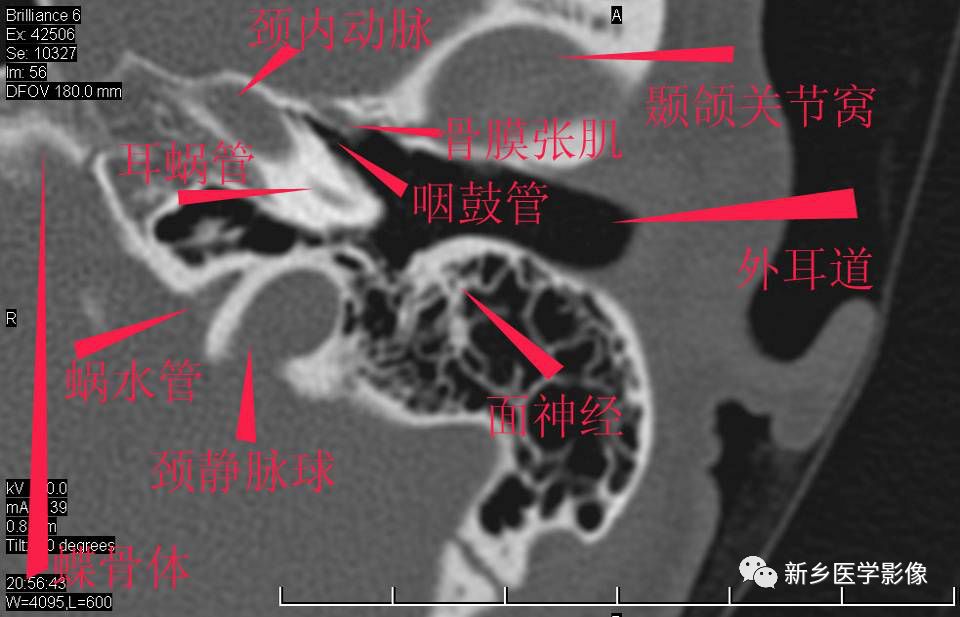

耳部详细解剖纯手工标注